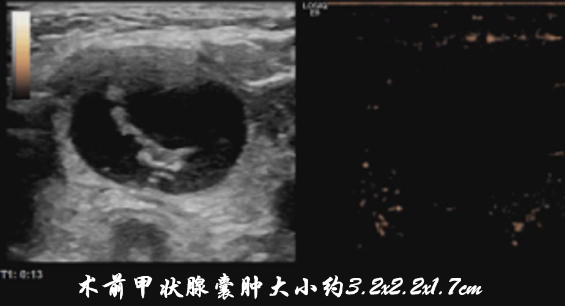

80岁的张奶奶5天前突然发现颈部肿物,还伴着明显胀痛,就诊于我院急诊外科。由于她患有高血压、糖尿病、冠心病等多种基础疾病,外科手术风险较高,医生随即建议转至介入与血管外科。王丽云副主任会诊后明确诊断:甲状腺右侧叶囊肿伴囊内出血,囊肿大小达4.0x3.2x2.6cm。考虑到患者高龄且基础病多,决定采用微创的甲状腺囊肿硬化治疗术,无需开刀、创伤小、恢复快,完美规避了传统手术的风险。